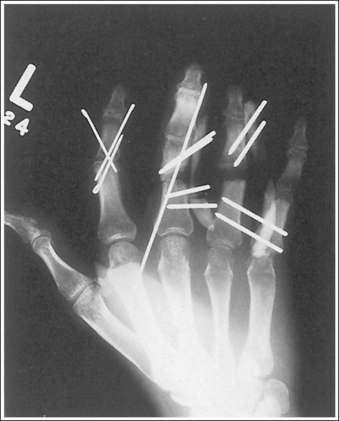

Hand: Posteroanterior Projection

Hand: Posteroanterior Oblique Projection (External Rotation)

Hand: “Fan” Lateral Projection (Lateromedial)